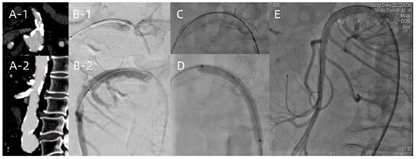

确诊后6 h,急诊行肠系膜上动脉球囊扩张成形及支架植入术(图2):局麻下右侧股动脉入路,高压造影、超选择造影见肠系膜上动脉起始部位重度狭窄接近闭塞;肠系膜上动脉起始段球囊预扩张成形(4~60mm EverCross Medtronic,美国),造影复查见残余狭窄90%,遂行自膨支架植入(6~60mm Everflex Medtronic,美国),造影复查见支架局部打开不满意、明显切迹、残余狭窄70%,遂行球囊后扩张成形(5~60mm EverCross Medtronic,美国),造影复查见残余狭窄20%;手术结束,时长2 h,患者全程配合可,返回普通病房。患者术后依诺肝素钠3000 IU q12h皮下注射抗凝联合阿司匹林100 mg qd口服抗血小板,头孢曲松1 g q12h静脉点滴抗感染,禁食水,肠外营养支持,监测生命体征及腹部症状。术后第1天体温(38℃)及血WBC(12.44×109/L)、CRP(104.28 mg/L)升高,第2天体温开始稳定(36~37℃)、血WBC下降至正常值范围、血CRP持续下降。术后第1天右下腹压痛较前加重,无肌紧张,胃肠外科会诊暂不考虑肠管坏死、继续保守治疗,第2天右下腹压痛减轻,第3天无压痛、反跳痛,出现排便,全过程始终有排气。术后第7天停用抗生素、循序恢复饮食。